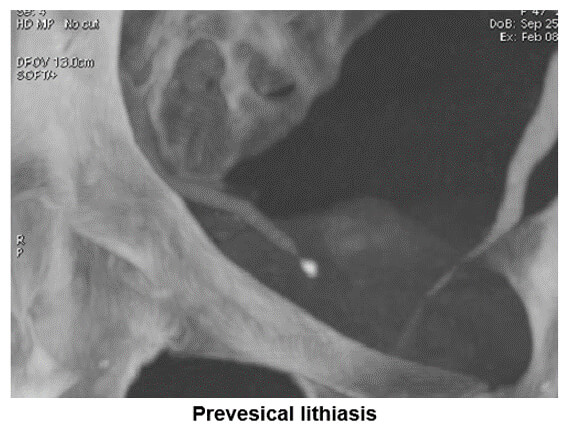

Lithiasis

You can see on this image an example of maximum intensity projection which is used to search for ureter stenosis caused by perivesical lithiasis.